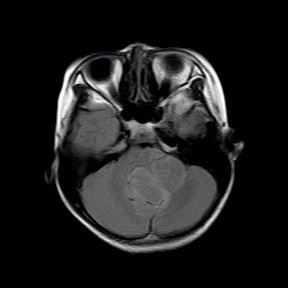

查体见四肢肌力V级,肌张力稍降低,腱反射减弱.生理反射存在,病理征未引出.闭目难立征(+),小脑共济失调征(+)。 头部MR所见:第四脑室内见一团块状稍长T1、稍长T2信号影,病灶大小约 48X33mm,病灶充满第四脑室,且向左侧桥臂侵犯,达左侧硬脑膜,病灶信号不均匀,其内可见点片状长T1、长T2囊性信号,DWI示未见明显异常受限,脑室系统明显扩张,增强扫描病灶呈轻度不均匀强化。双侧侧脑室周围白质见条状FLAIR高信号,边界不清。脑沟、脑裂变窄,中线结构居中。颅骨未见明确骨质破坏。左侧上颌窦、筛窦粘膜增厚。矢状位示垂体形态、信号未见明显异常。